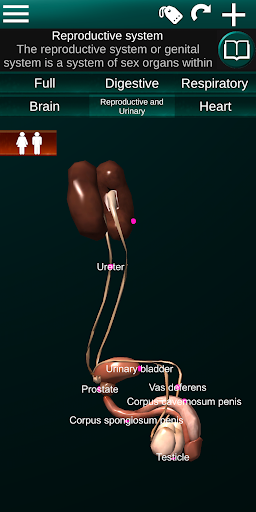

Toont een 3D-anatomisch model van de belangrijkste organen van het menselijk lichaam en een beschrijving van elk orgaan.

* Voortplantingssysteem, dat de mannelijke en vrouwelijke voortplantingsorganen omvat.

* Gemakkelijk te openen en te navigeren (zoom, 3D-rotatie).

* Vergelijk mannelijke en vrouwelijke organen.

* Beschrijvingen van elk orgel.